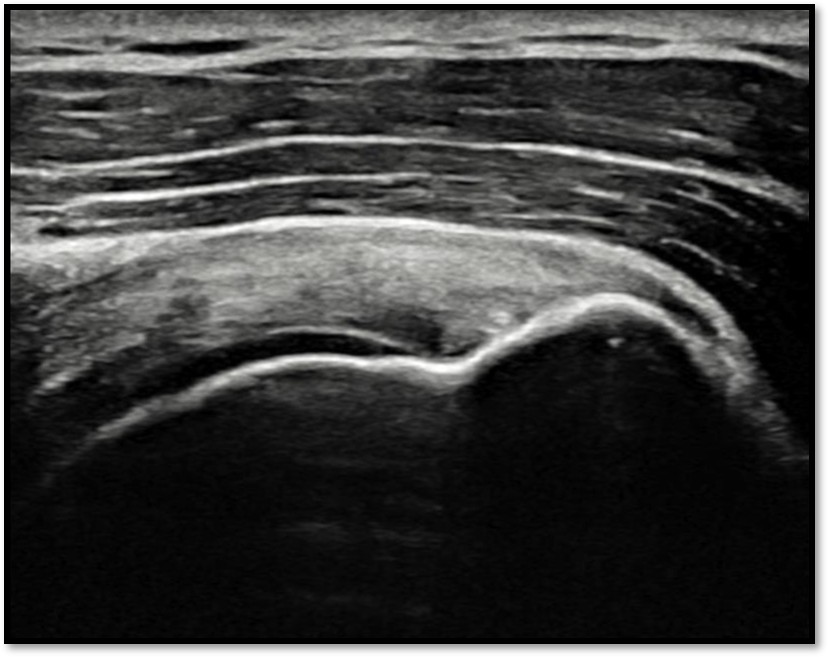

케이스 2: 점액낭면측 파열 → 리제네텐

환자: 38세 여성, 필라테스 강사

진단:

MRI: 극상건 점액낭면측 부분파열 (약 35%)

인대 얇아짐 소견

치료:

리제네텐 콜라겐 패치 적용

재생주사 병행

결과:

16주 후 MRI: 인대 두께 증가 확인

필라테스 강의 복귀